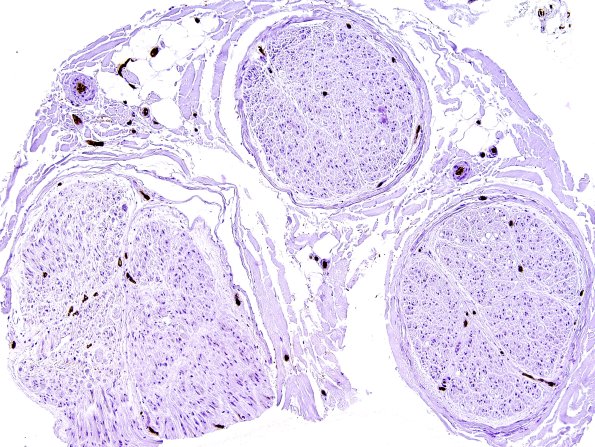

6A2  (Case 6)  Ulex 1

The vasculature stained with the endothelial lectin marker Ulex europaeus (Ulex IHC)